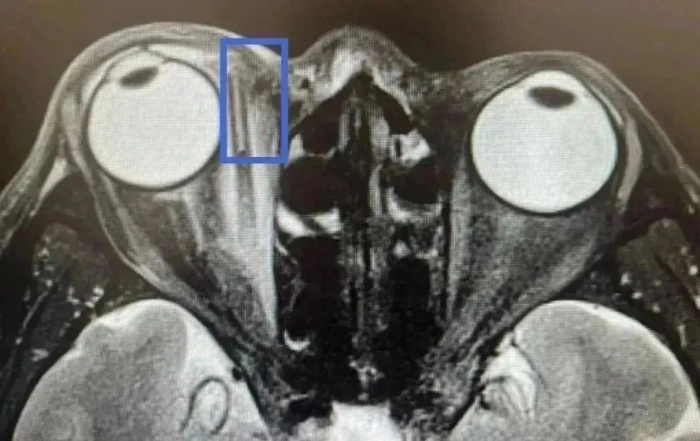

詳細(xì)詢(xún)問(wèn)受傷過(guò)程時(shí),王老伯始終否認(rèn)有異物進(jìn)入眼里。但眼眶磁共振檢查顯示,王老伯右眼深處內(nèi)支肌旁有一長(zhǎng)條異物。

當(dāng)天,張宗端主任立即為王老伯施行眶內(nèi)異物取出+清創(chuàng)縫合術(shù),術(shù)中取出如筷子粗,長(zhǎng)約3厘米的樹(shù)枝。